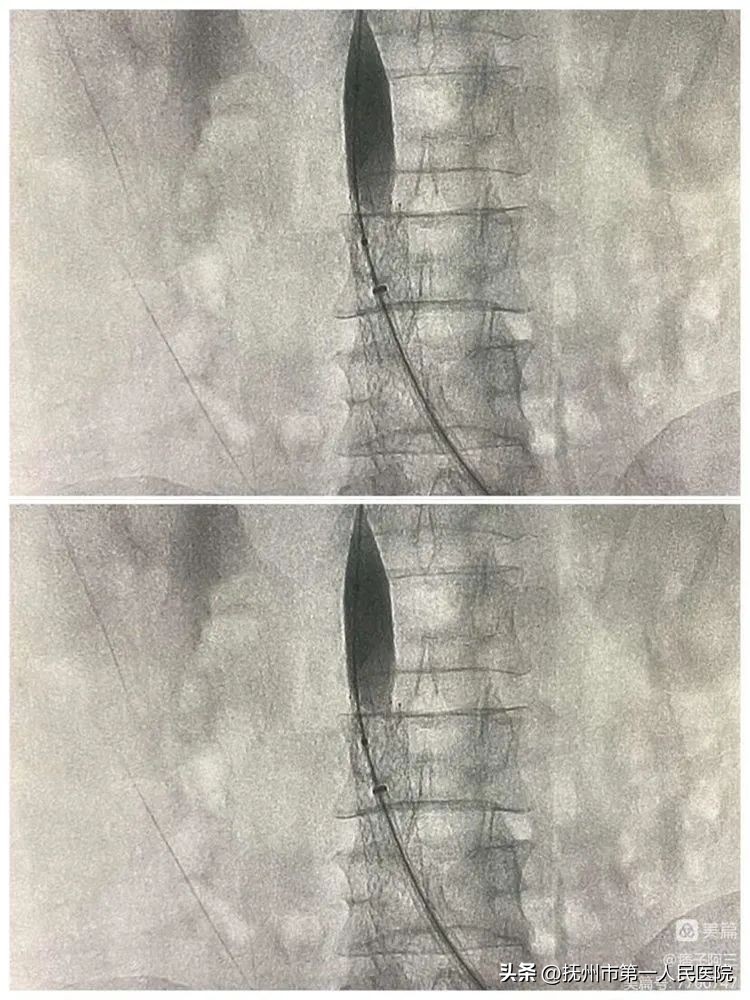

10分钟后再次造影发现、下腔静脉回缩再次狭窄、患者下腔静脉长段闭塞狭窄遂行下腔静脉支架植入

支架植入术中造影

并给予F14球囊内扩